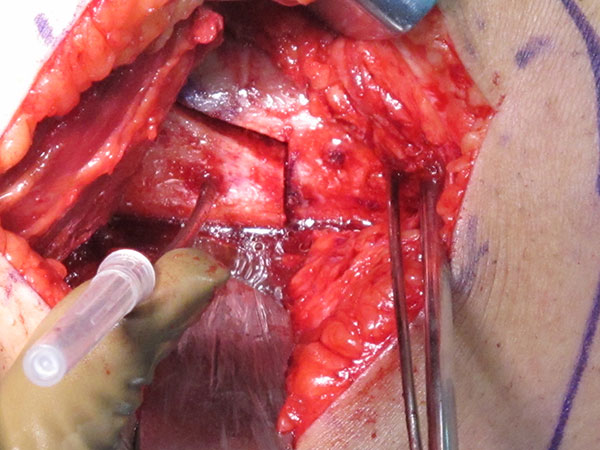

Varising Derotational Distal Femoral Osteotomy